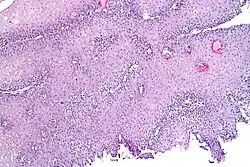

Diagnostic investigations for the evaluation of heartburn include endoscopy and esophageal pH monitoring. GERD is commonly diagnosed based on symptoms of heartburn or regurgitation. Endoscopy may be used to evaluate people who do not respond to treatment for heartburn or those with alarm symptoms such as persistent vomiting, gastrointestinal bleeding, iron-deficiency anemia, involuntary weight loss, difficult/painful swallowing (dysphagia, odynophagia), epigastric mass, family history of esophageal or gastric cancer, and new onset of symptoms in those older than 50 years of age.[23]

Endoscopy is a method used to detect abnormalities in the esophageal lining such as erosive esophagitis and Barrett's esophagus. Biopsies taken during an endoscopy can help assess for other conditions linked to heartburn, such as eosinophilic and lymphocytic esophagitis.[14] The esophageal 24-hour pH test or the multichannel intraluminal impedance-pH test is often performed in those with refractory heartburn who have undergone an endoscopy. High-resolution esophageal manometry (HREM) is the standard test for diagnosing esophageal motor disorders. It helps rule out major motility issues in those with persistent heartburn who have normal endoscopy and pH testing. Motility disorders include achalasia, esophagogastric junction outflow obstruction, diffuse esophageal spasm, jackhammer esophagus, and absent contractility. HREM can also distinguish GERD from conditions like rumination and supra-gastric belching. In some cases, gastric scintigraphy may be used to detect gastroparesis.[24]